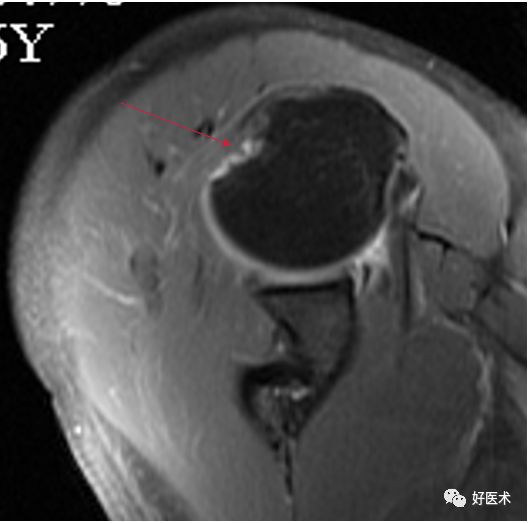

MR间接关节造影1.5T轴位T1W脂肪抑制